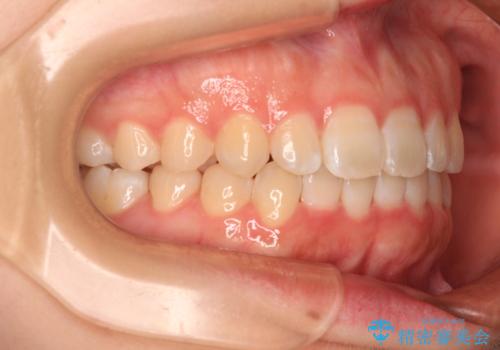

前歯のデコボコを整える インビザラインによる矯正治療

- 上下前歯のデコボコを気にして来院された患者様です。

叢生は軽度であり、ワイヤー矯正でもマウスピース矯正でも対応可能であったので、好きな装置を選んでもらいました。

相談の結果、インビザラインによる矯正治療を行うこととしました。

毎日の装着時間をしっかりと守っていただいたことで、1年程度で無事に治療を終えることができました。